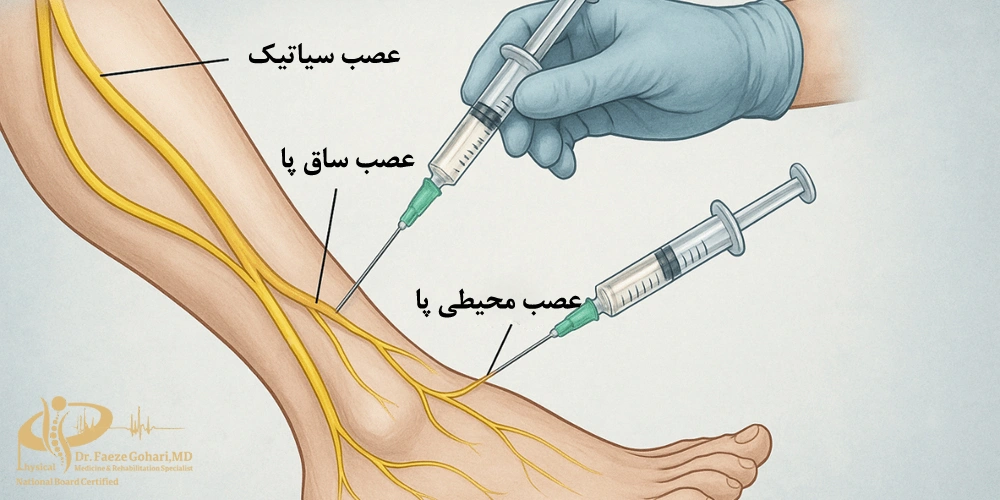

اندام تحتانی (ران، زانو، ساق، مچ و کف پا)

بلوک عصبی سیاتیک تحت هدایت سونوگرافی

بلوک عصبی در اندامهای تحتانی یکی از روشهای مهم برای کاهش درد و کمک به توانبخشی در بیماریها و آسیبهای لگن، ران، زانو، ساق و پا محسوب میشود. در این روش دارو (بیحسی موضعی، کورتون یا ترکیب آنها) بهطور هدفمند در اطراف عصب یا شبکههای عصبی اصلی این نواحی تزریق میشود تا انتقال پیامهای درد متوقف شود و التهاب کاهش یابد (منبع).

- درد ساق و پا: ناشی از گیر افتادن عصب سیاتیک یا تیبیال

| درد ساق و پا |

| اثر و ماندگاری |

| بلوک اعصاب سیاتیک یا تیبیال برای کاهش درد تیرکشنده یا دردهای نوروپاتیک در ساق و پا استفاده میشود. این روش میتواند هم جنبه تشخیصی داشته باشد و هم در کاهش درد مقاوم به دارو مؤثر باشد. ماندگاری از چند روز تا چند هفته. |

نحوه انجام بلوک عصبی اندامهای تحتانی

بلوک عصبی در اندامهای تحتانی یک روش کمتهاجمی سرپایی است که با هدف کاهش درد و التهاب و همچنین تشخیص منبع درد انجام میشود. بسته به محل درگیری، عصبهای مختلفی مانند اعصاب ژنیکولار زانو، سیاتیک، تیبیال، فمورال یا شبکه کمری و پودندال میتوانند هدف تزریق باشند. اساس کار این است که دارو در اطراف عصب قرار گیرد تا انتقال پیامهای درد موقتاً متوقف شود و بیمار بتواند فعالیتهای روزمره و توانبخشی را راحتتر ادامه دهد.

پزشک با توجه به معاینه و تصویربرداری عصب مرتبط با درد را مشخص میکند؛ برای مثال ژنیکولار برای آرتروز زانو یا سیاتیک برای درد تیرکشنده پا - آمادهسازی بیمار

مسیر سوزن با کمک سونوگرافی یا در برخی موارد فلوروسکوپی تعیین میشود تا تزریق دقیقاً در اطراف عصب انجام گیرد. - وارد کردن سوزن و تأیید موقعیت

سوزن باریک به آرامی به سمت عصب هدف هدایت میشود. گاهی از مقدار اندکی ماده حاجب یا تحریک عصبی (Nerve stimulation) برای اطمینان از محل صحیح استفاده میشود. - تزریق دارو

داروهای بیحسی موضعی، کورتون یا ترکیب آنها بهتدریج در اطراف عصب تزریق میشوند تا التهاب کاهش یافته و انتقال پیام درد مهار شود. - پایش کوتاهمدت و ترخیص